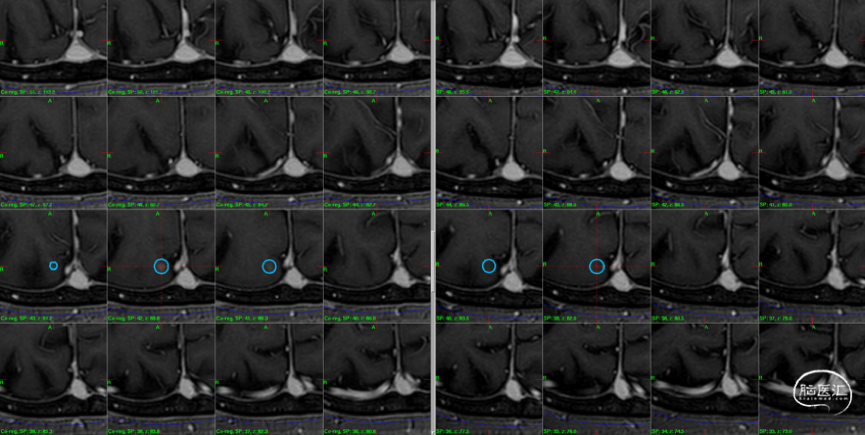

制定立体定向伽玛刀治疗计划(术中薄扫核磁扫面共发现4个病灶,除术前的2个病灶外,还发现2个小病灶);

影像随访:

6个月随访时,薄扫增强磁共振(1mm/层)提示肿瘤明显缩小,无放射相关不良反应,没有新发病灶;患者目前仍在规律的随访当中,期待我们的长期随访结果。